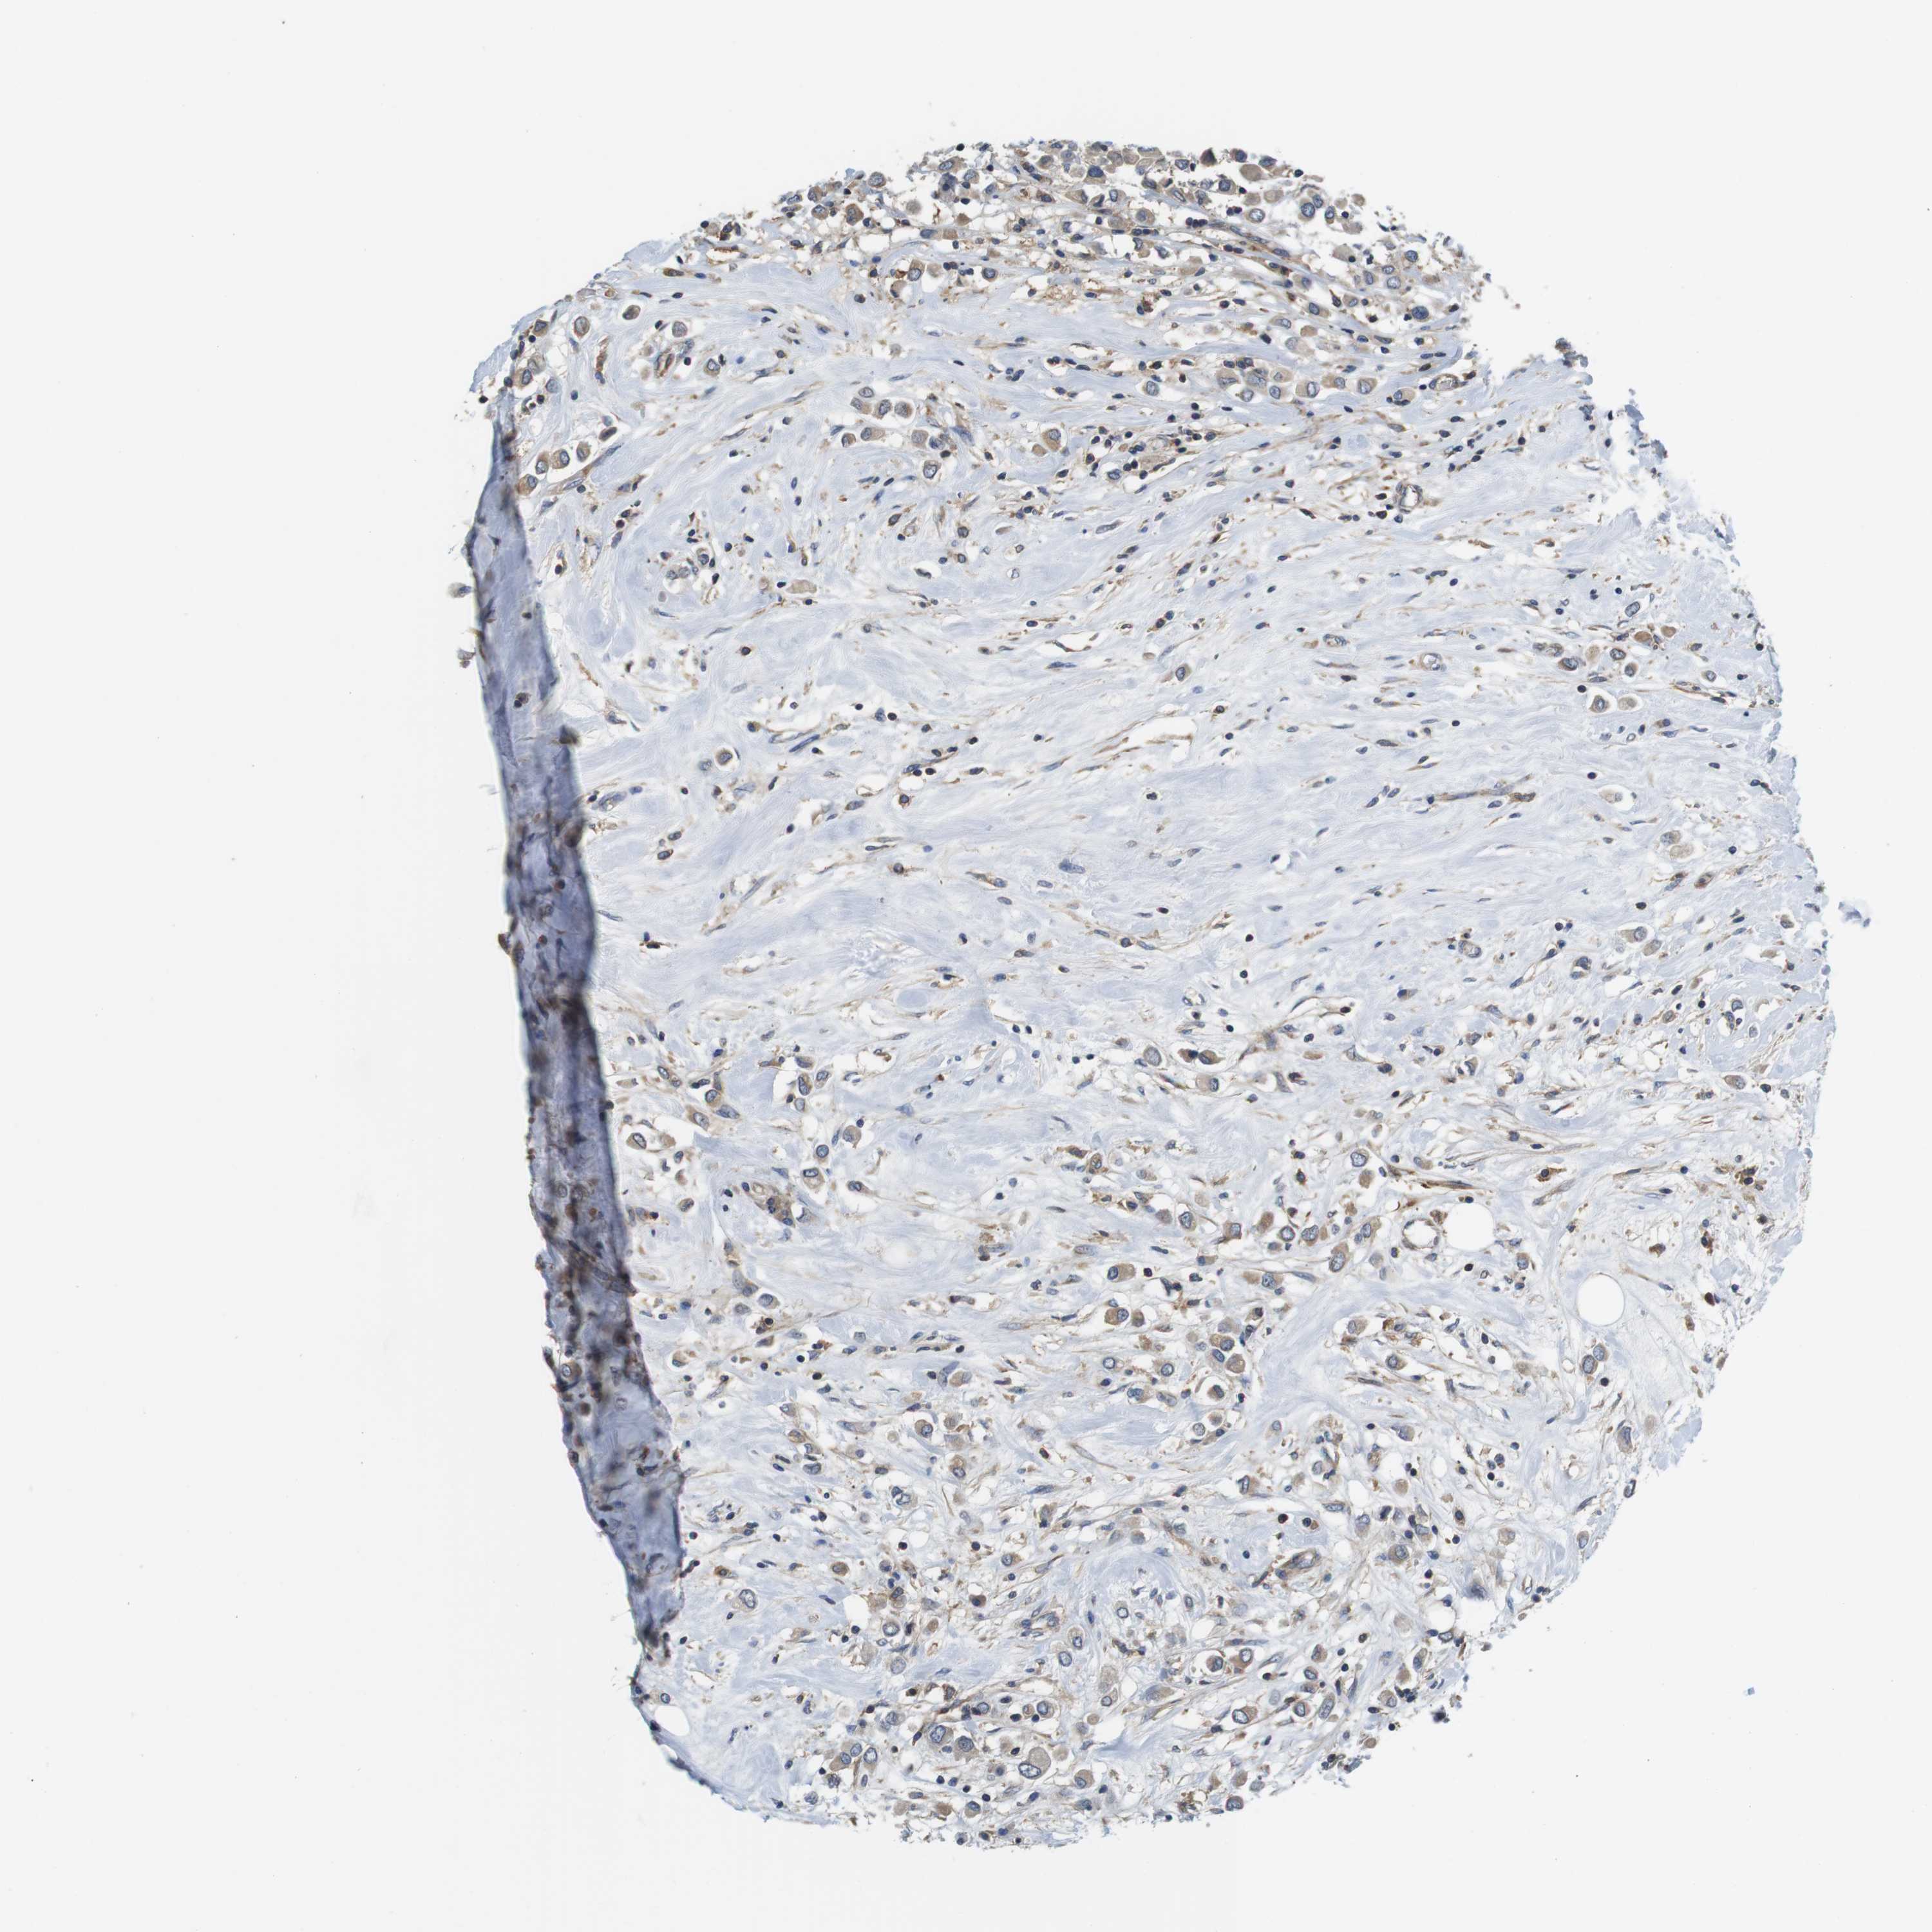

CANCER BREAST CANCER Show tissue menu

BRCA TCGA BRCA VALIDATION PROTEIN EXPRESSION